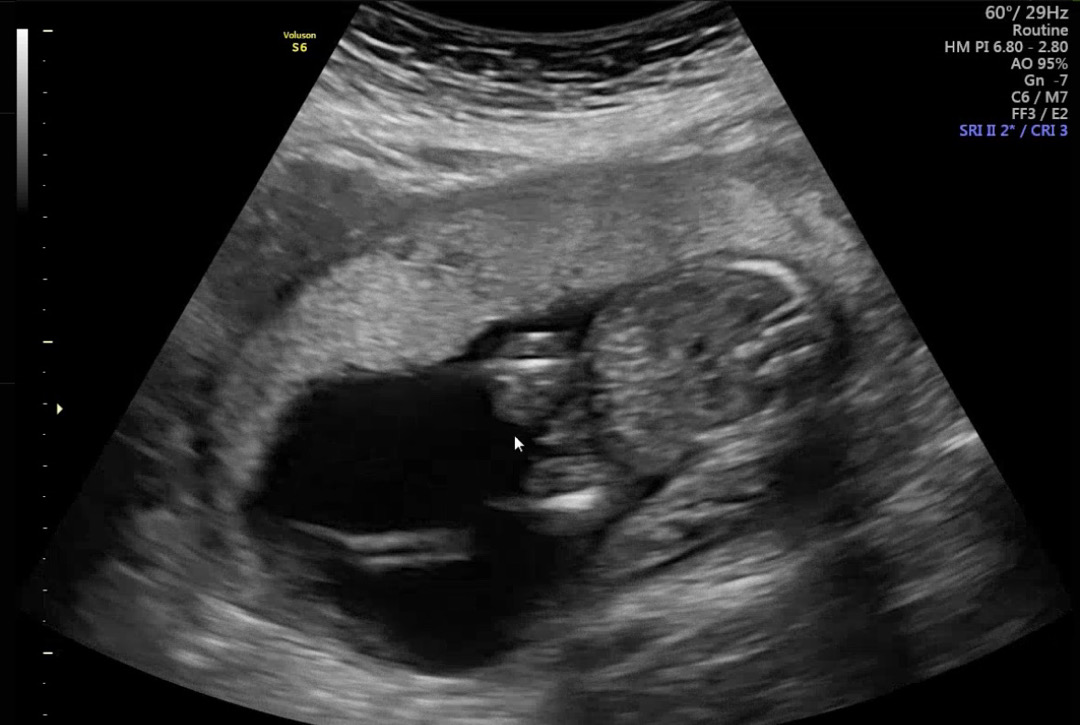

16주 2차 기형아 검사 하러 갔어요 아기가 엎드려있어서 확실하게는 말 못하겠다고 하시더라구요ㅜ 근데 다리 사이에 뭐가 있는것 같은데ㅜㅜ 아들일까요? 첫째는 아들이고 7살 차이나는 둘째인데 첫째랑 너무 다른 입맛으로 딸이라고 너무 단정짓고 있어서 그랬나요 눈물 낫어요ㅠㅠㅠㅠ애기에겐 미안하지만 ㅠㅠㅠ